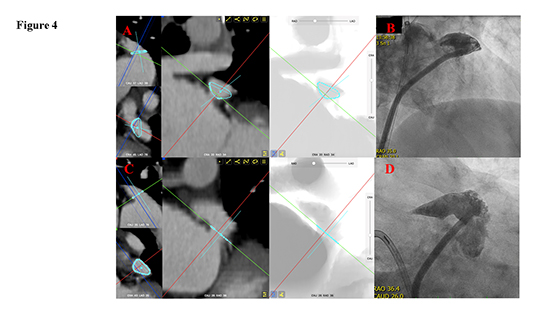

Figure 4. Examples of the assessment of and the individualized projection angles for a patient with an superiorly-posteriorly (atypically) located LAA

In a patient with a atypically (posteriorly, or backward orientated, lying on the top of the atrium) appendage, the optimal viewing fluoroscopic angle differed significantly from the projection angles recommended by the manufacturer. In the standard RAO30° - CRA20° projection, only the proximal part of the LAA was visible, creating an image of a “bud” during LAA angiography.

On cCT, personalized viewing fluoroscopy angles were searched for each particular LAA in different combinations of RAO projections with different cranial and caudal projections. The aim was to test for how many patients the fluoroscopic projections recommended by the manufacturer will be acceptable. The RAO 30°, in combination with CRA 10–20° or CAUD 10–20° provided at least one acceptable projection in most patients (22 pts., 88%), although FluoroCT analysis allowed to find the best personalized viewing angle in this relatively broad angle range. However, in patients with the LAA lying superiorly and posteriorly, i.e. LAA with an early posterior angulation lying “backward” on the roof of the left atrium and instead lying superiorly-anteriorly and pointing toward the left ventricle, the optimal fluoroscopic projections differed substantially with greater RAO and CAUD angles being needed. An example of a posteriorly oriented LAA is shown in [Figure 4]; in this particular patient, the optimal viewing angle, analyzed using FlouroCT, was RAO36° - CAUD 26° that was also finally used for implantation [Figure 4].